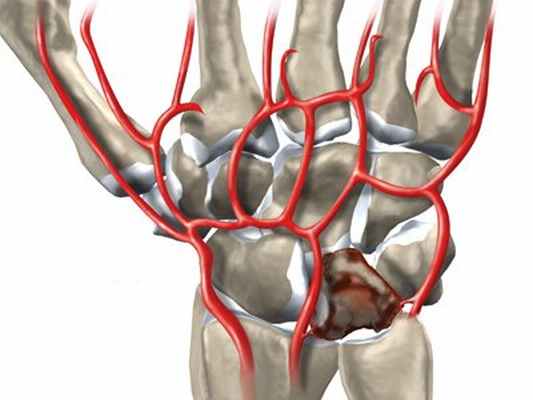

По всей видимости, нет одной точной причины для нарушения кровоснабжения, что приводит к некрозу полулунной кости. Болезнь Кинбека вызвана многими факторами. Эти факторы могут быть связаны с притоком крови (артериальные проблемы), с оттоком крови (венозные проблемы) или особенностями строения костей. Варианты строения костей, предрасполагающие к болезни Кинбека, — это относительное укорочение локтевой кости и особенности строения самой полулунной кости. Некоторые случаи могут быть ассоциированы с подагрой, серповидно-клеточной анемией или церебральным параличом.

Травма, единичная или регулярно повторяющаяся, также может вызвать некроз полулунной кости. В целом, все же, не существует достоверных данных о том, что болезнь Кинбека может считаться профессиональным заболеванием. Следует заметить, что нарушение кровоснабжения полулунной кости накладывает свои особенности на лечение травм запястья и безусловно влияет на прогноз.

Считается, что причиной развития заболевания может служить однократная травма (падение на ладонь или кисть), а также постоянная травматизация (микротравматизация), что может привести к нарушению кровоснабжения костей запястья.

Сущность болезни состоит в постепенно нарастающем асептическом некрозе (или, точнее остеонекрозе) полулунной кости, который со временем приводит к ее фрагментации и полному разрушению. Все это сопровождается болью в запястье, в области лучезапястного сустава. Боль усиливается при движениях и возрастает по мере прогрессирования заболевания.

Некроз полулунной кости приводит к отмиранию костной структуры полулунной кости. Одной из причин этого является снижение кровоснабжения полулунной кости. Зачастую заболевание вызвано несколькими факторами, например, слишком короткой локтевой костью и меньшим суставным углом лучевой кости, что приводит к дополнительной повышенной передаче усилия на полулунную кость.